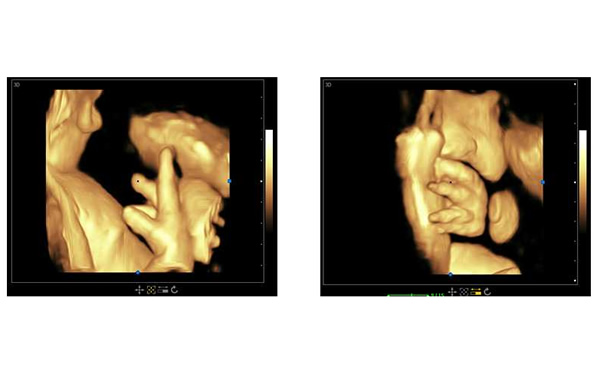

孕期B超檢查三個階段,大為醫療高端彩超孕期胎兒顯示

醫院用高端三維多普勒、4D成像技術的彩超可以參考大為醫療的高端彩超。